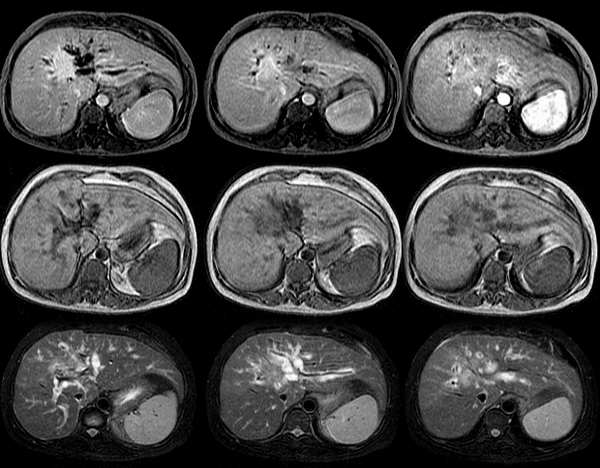

肝癌的诊断报告单图片

肝癌检查报告单图片